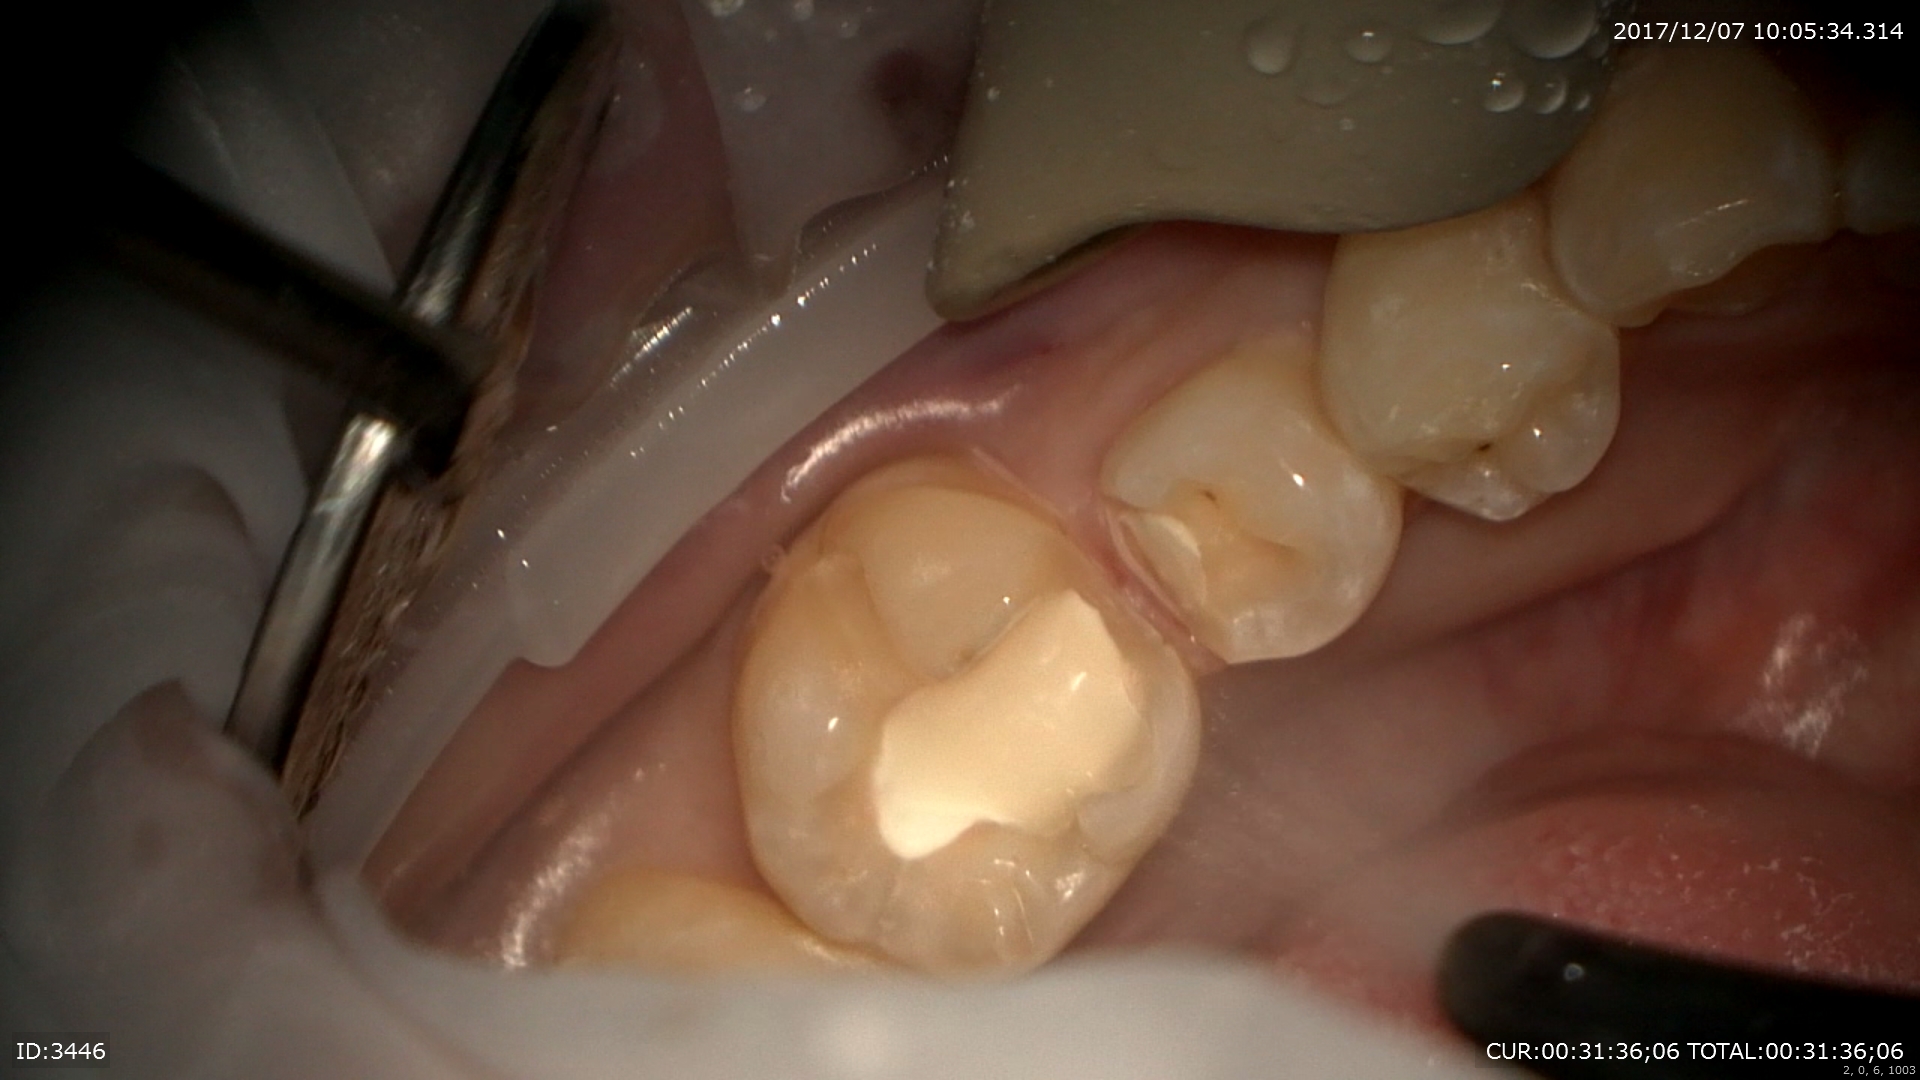

神経に近い部分は後遺症が残るのでMTAセメントで覆い

二重で壁を作成

型取りの前

これで神経も守れる。後遺症もほぼないと思います、術中もマイクロスコープのお蔭で無痛